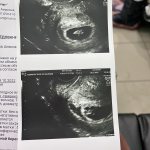

Девчат у кого так было !? Нормально ли беременность проходила ? Узист сказала что это не отслойка , отслойка выглядит по другому . Что мол это нормально , бывает такое. Выделения нормальные , ни кровит ниче . На учет пойду вставать в понедельник , все ровно переживаю как ни как хоть она и сказала что хорошо, но сказала что во время секса быть аккуратным просто и все

Матка и должна быть расширена вы ж беременны .все нормально . Главное теперь берегите себя ! И я вас поздравляю!